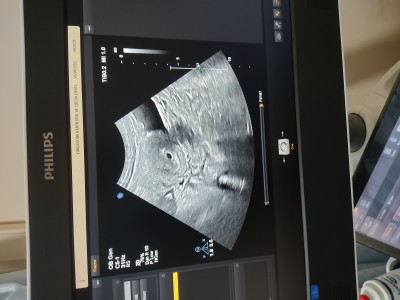

haftaya gel içinde bebek varmı kalp atışı varmı bakalım dedi zaten stresliyim bide insanlar geriyo beni herkese söylemedim bı kaç kişiye söyledim onlarda yetti içinde bebek yokmu diyolar 4.6 şuan normal demi ilk kese goruluyo zaten haftaya kadar vakit geçermi bilmiyorum

Hayırlı olsun alttan mi baktı canım

Yok canım üstten

Ne  güzel  görünmüş maşallah canım Allah sağ salim kucağına almayı nasip etsin

Siyah olan bebek bence

Yok kese o canim